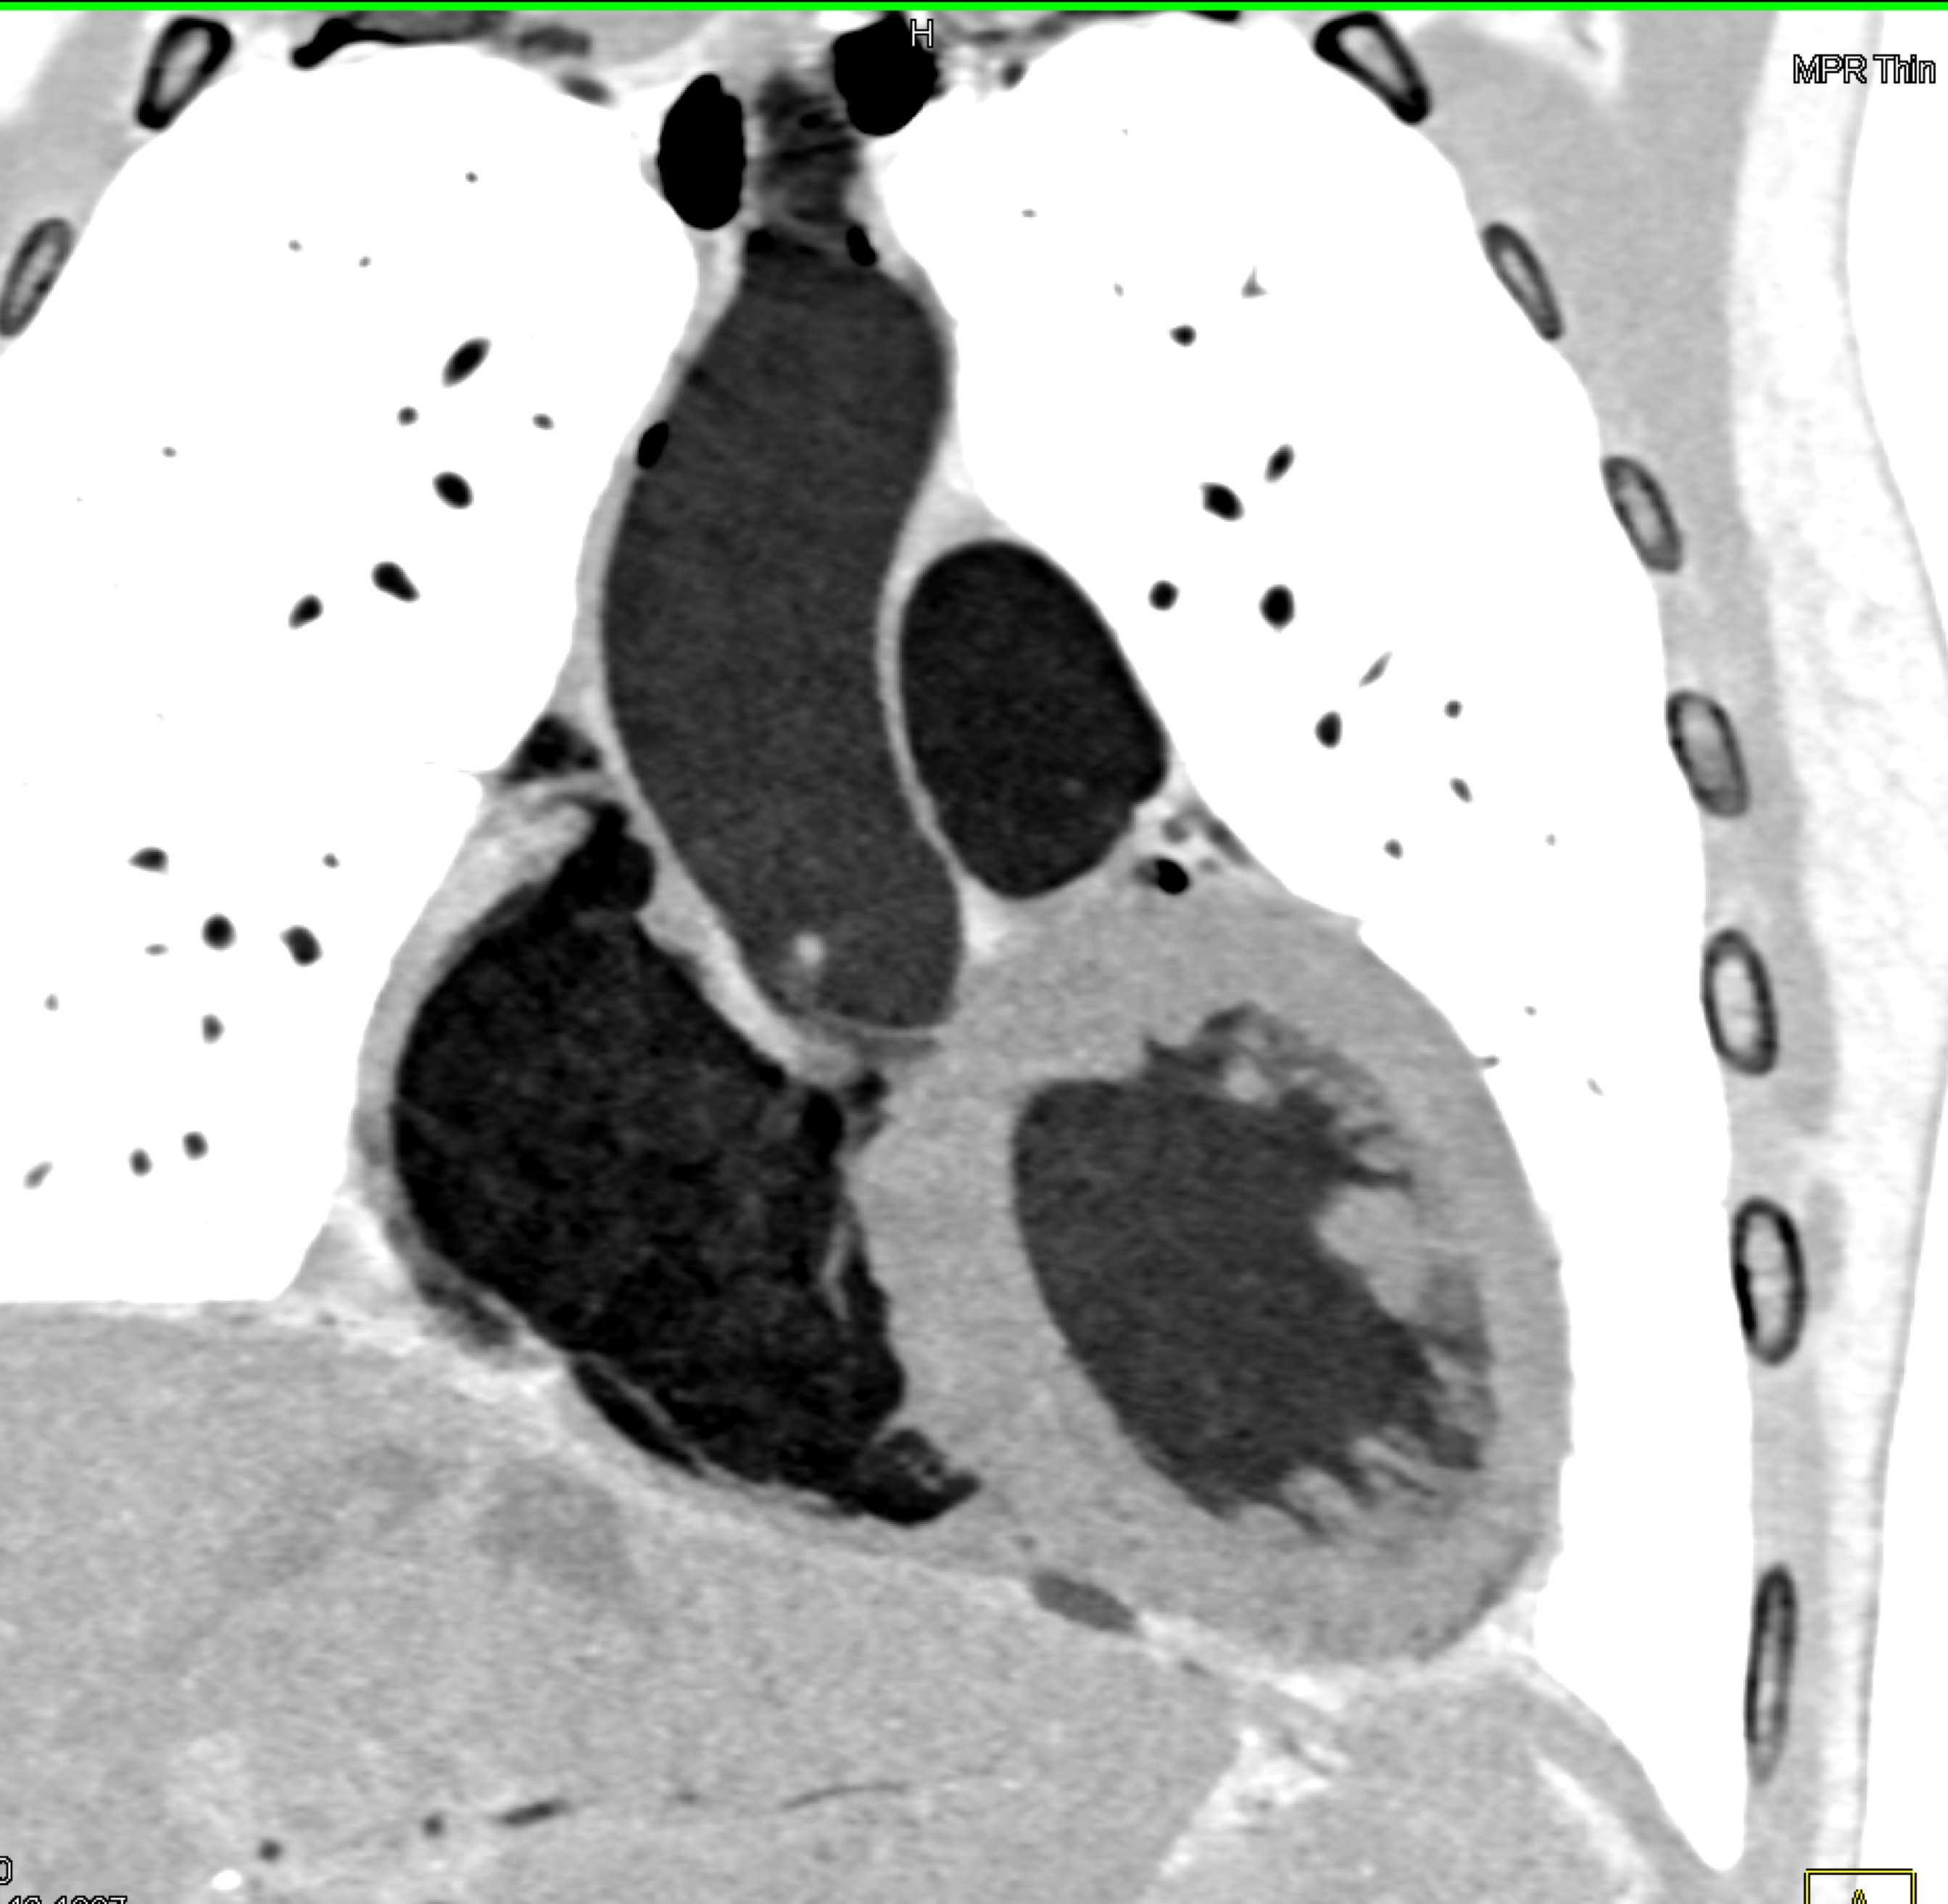

- Select the best answer

- Submit your answers by selecting the "Submit" button at the end of the quiz.

6) The most likely diagnosis in this case is?

vegetations in pulmonary valve

failed pulmonic valve

normal appearance of repaired pulmonary valve

abscess of the pulmonary artery